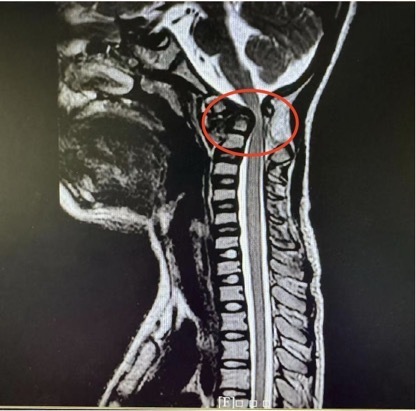

术前磁共振(脊髓明显受压),术后磁共振(脊髓受压解除)。

经院方详细检查后,王亮主任团队发现,乐乐的寰枢椎脱位是由游离齿突引起。虽然从影像学上看没有明显的复位障碍,适合进行后路复位固定手术,但在进一步的颈椎CT检查后,王亮主任团队却发现了棘手的问题:患儿异常细小的颈椎解剖结构使得手术置钉难度倍增。

为解决这个问题,脊柱外科一科主任王亮在术前采用3D打印技术复刻了乐乐的寰枢椎模型,反复进行充分的手术模拟。几次模拟下来,王亮有了信心,决定直接实施颈椎后路手术复位手术。术中,团队紧密配合,将手术精度控制在“毫米级”,一次性精准置钉,完成寰枢椎复位与固定。